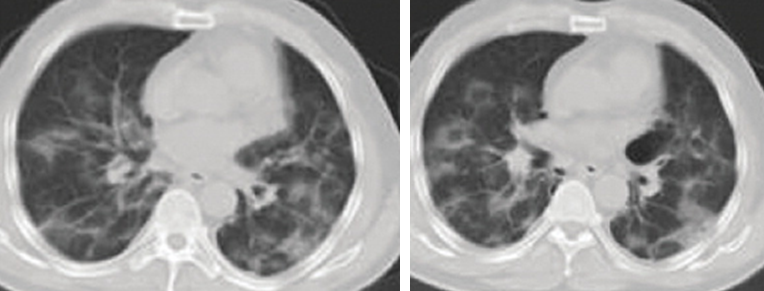

Case 2: Male, 60 years old, resident of Wuhan, presented to the district hospital with fever and rigors, dry cough, aching muscles, breathlessness, fatigue, bloating, and anorexia since 17 January 2020. His CT scan showed an infective appearance in both lungs, and a diagnosis of viral pneumonia was suspected. He received unknown outpatient treatment.

• The patient was discharged with complete clinical and laboratory resolution and almost complete radiological resolution on 10 February 10, 2020.